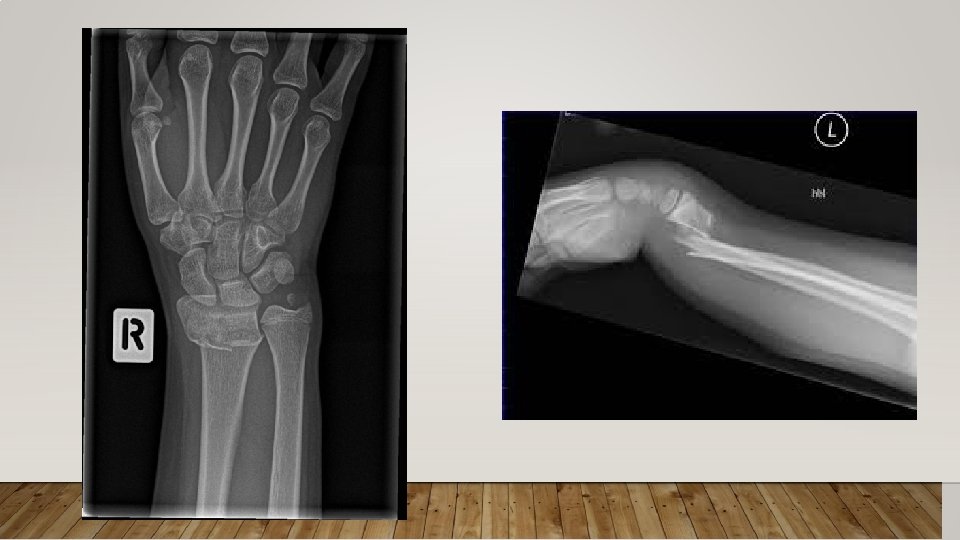

WRIST AND FOREARM FRACTURES • Colles’ Fracture: fracture of the distal end of the radius • Most commonly caused by fall on a stretched hand • Scaphoid fracture is less commonly in patient with osteoporosis

X-RAY • X-ray is an obsolete modality to diagnose or screen osteoporosis • No positive findings unless that you lost almost 50% of your bone density